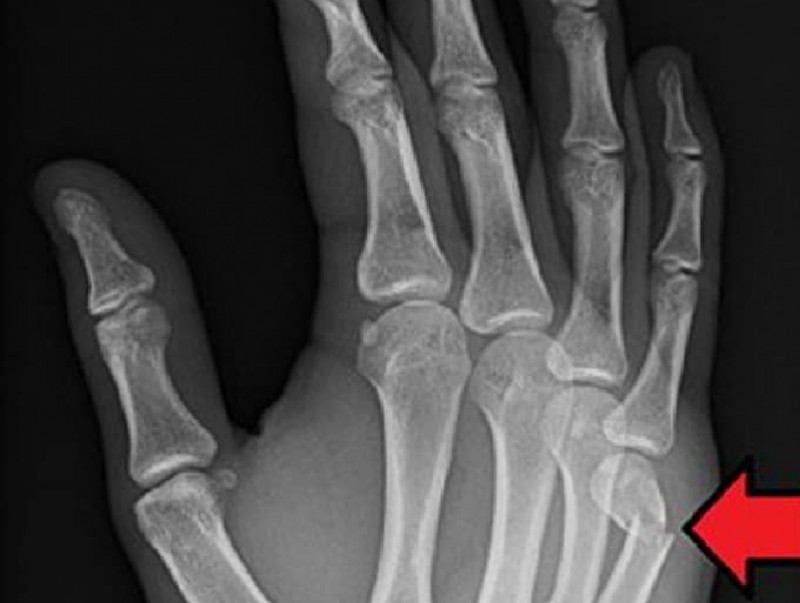

Гэмтэл, согог судлалын үндэсний төвийн Гар сарвуу нөхөн сэргээх бичил мэс заслын тасгийн эрхлэгч Л.Нанжид: “Сээрний ясыг гараараа цохих нь шууд утгаараа, ясыг ясаар цохиж байгаа хэрэг. Мэдээж аль нэг яс нь хугарна. Сээрний яс хугарах нь хэнд ч хамаагүй, үр өгөөжгүй. Харин тухайн хүний өөрийнх нь яс хугарвал хохиролтой. Мөн зөөлөн эд гэмтсэнээр хаван, хавдар үүсэж нян бактери бий болно. Үүнээс болж гараа тайруулах ч эрсдэлтэй. Ямар нэг гадны шалтгаангүй, зүгээр байж байгаад энэ мэт өөрийгөө гэмтээж хохирох, эмч нарын ачааллыг нэмэх нь асуудал дагуулж байна.

Зарим залуус “Өөрийнхөө гараар юу хийх нь өөрт чинь хамаагүй. Эмчилж эдгээх нь чиний хийх ёстой ажил" гэсэн байдлаар хандах нь бий. Гэхдээ ямар ч ач холбогдолгүй зүйл \сээрний яс\-ээс болж өөрийгөө гэмтээхгүй байгаасай, өөрийгөө бүү хохироогоосой гэсэндээ л эмч нар сэрэмжлүүлэг, зөвлөмж өгдөг юм шүү” гэв.